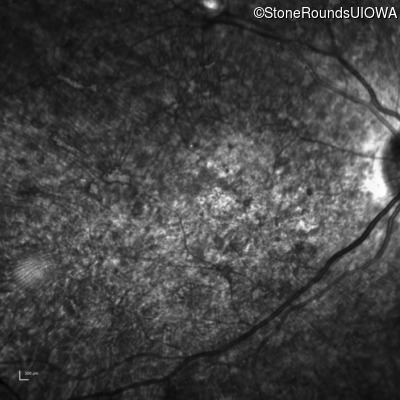

Infrared Fundus Photograph - Right - 20/400 sc

Exemplar